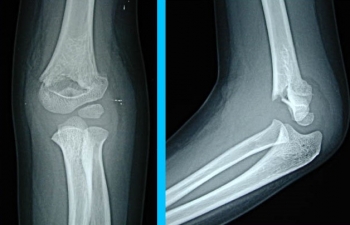

上腕骨顆上骨折

上腕骨顆上骨折は、上腕骨の遠位端部分(肘の近く)の骨折です。

上腕骨顆上骨折の診断

X線写真が必要です

上腕骨内顆骨折、上腕骨外顆骨折など、類似した骨折もありますし、骨折の折れ方も程度がありますので、必ずX線写真を撮ってください